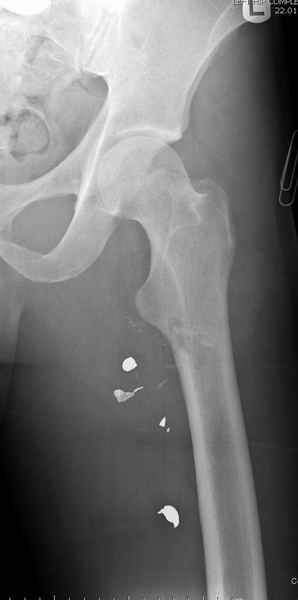

Больной с огнестрельным переломом бедра с вовлечением около 15% медиального кортекса, входное отверстие около 1 см в диаметре; стабильный, без сосудистых и неврологических признаков.

Входные маленькие отверстия от ранении просто игнорируются, никаких дренажей, как любое колотое ранения, они закрываются и были случаи через месяц. Конечно, ведется профилактика открытых ранении: сыворотки и т.д., но еще самое главное уделяем профилактике образования перелома из-за стресса в результате дефекта кортикального слоя.

Литературные данные о влиянии кортикального дефекта на стрессовые переломы в длинных трубчатых костях в основном встречаются в онкологии, например кортикальный дефект более 50% имеет больше шанса стрессовых переломов, чем в нашем случае.

Учитывая, что больной получил травму не во время визита в церковь, и он является одним из представителем 40 миллионного “outstanding itizen”, без медицинской страховки, без работы в свои 39 лет, и без надлежающей ортопедической дисциплины у которого отсутсвует страх стрессового перелома, было рекомендовано оперативное лечение: профилактическое антеградное интрамедуллярное штифтование.

Выглядит агрессивно, и обычно госпиталь, беря финансовые расходы, остается в убытке, но мы всё же посчитали, что издержки от штифтования намного меньше, чем возможные финансовые и моральные издержки лечения таких больных, но с осложнением.

Методика штифтования при отсутствии большой зоны перелома как при онкологических профилактических штифтованиях, расверливание интрамедуллярного канала проводим с предварительным наложением дополнительного дренажного отверстия в дистальном отделе бедра (в данном случаи в канале оставили 6.5 мм канюлированный шуруп), иначе при создании давления в канале во время сверления имеется опасность эмболизации легочной артерии тромбом.